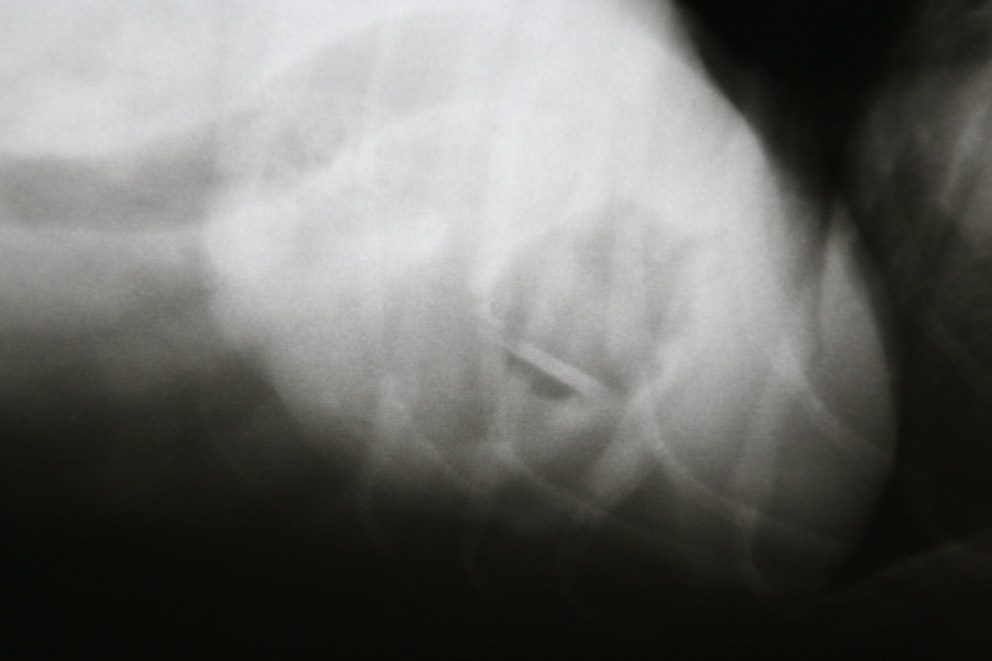

en op de andere foto’s wel: